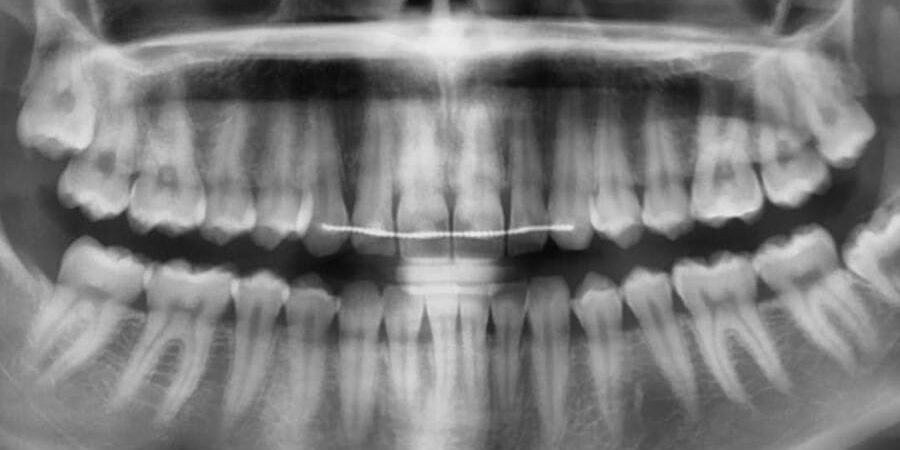

Az intraorális röntgen a leggyakoribb típusú fogászati röntgen. Az „intraorális” szó azt jelenti, hogy szájon belüli, ami itt arra utal, hogy a röntgenfelvételek a száj belsejébe helyezett készülék segítségével készülnek el.

Az eljárás egy, vagy pár fog rendkívül részletes feltérképezését teszi lehetővé, pontosan megmutatva az üregeket, a gyökereket, a csontszinteket és a környező szöveteket stb.

- a bitewing röntgenfelvételeket, amelyek a felső és alsó fogak koronáit együtt mutatják (jól alkalmazható a fogak közötti üregek és a csontvesztés kimutatására),

- a periapikális röntgenfelvételeket, amelyek a teljes fogat mutatják a koronától a gyökércsúcsig (jól alkalmazható fertőzések, tályogok, gyökérproblémák esetén), valamint

- az occlusalis röntgenfelvételeket, amelyek az állkapocs egy részének nagyobb képét mutatják (alkalmasak beékelődött fogak, többletfogak, állkapocs fejlődésének vizsgálatára stb.).